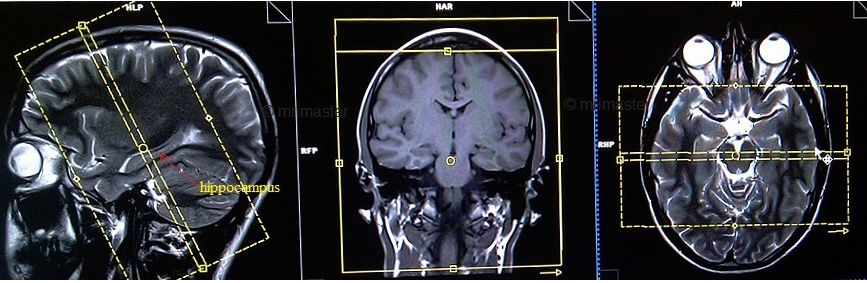

çocuklara ve bebeklere emar çektirirken tamamen hareketsiz şekilde kalmasının mümkünatı olmamasından dolayı çocuk ve bebeklerde anestezi yardımı ile emar çekimi yapılır. çekilen emar süreleri ortalama 15 dakika ile 1 saat arasında sürmektedir. Emar mr yani manyetik rezonans görüntüleme mrg vücutta ayrıntılı resimler oluşturmak için güçlü mıknatıslar radyo dalgaları ve bilgisayarın kullanıldığı bir testtir emar sıklıkla hastalıkları teşhis etmek veya tedaviye verilen yanıtı takip etmek için kullanılır. Her sağlık kuruluşundan emar çektirme işlemi yaptırılmamalıdır.